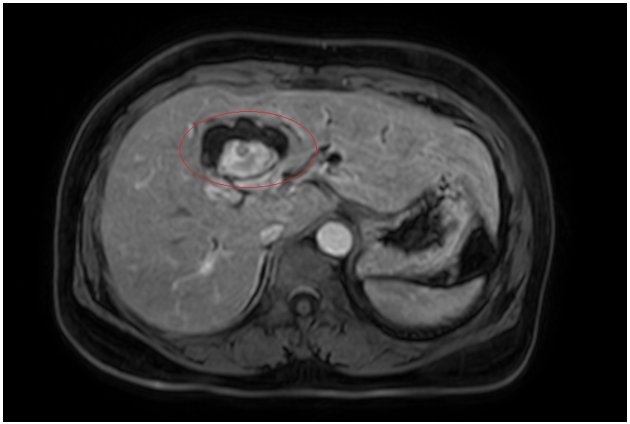

Đánh giá tổn thương trên phim chụp cộng hưởng từ: Nhu mô hạ phân thuỳ IV có ổ tổn thương dạng dịch, kích thước 38x52mm, trong có vài sỏi, sỏi lớn nhất kích thước ~27x37mm, có thông với nhánh đường mật gan phải lân cận, ngấm thuốc viền sau tiêm, chèn ép ngã ba đường mật, gây giãn đường mật trong gan hai bên

Hình 2. Hình ảnh giãn khu trú đường mật gan trái, tạo cấu trúc dạng nang và sỏi đường mật bên trong( vòng tròn đỏ), chèn ép kèm giãn đường mật trong gan hai bên trên phim chụp MRI